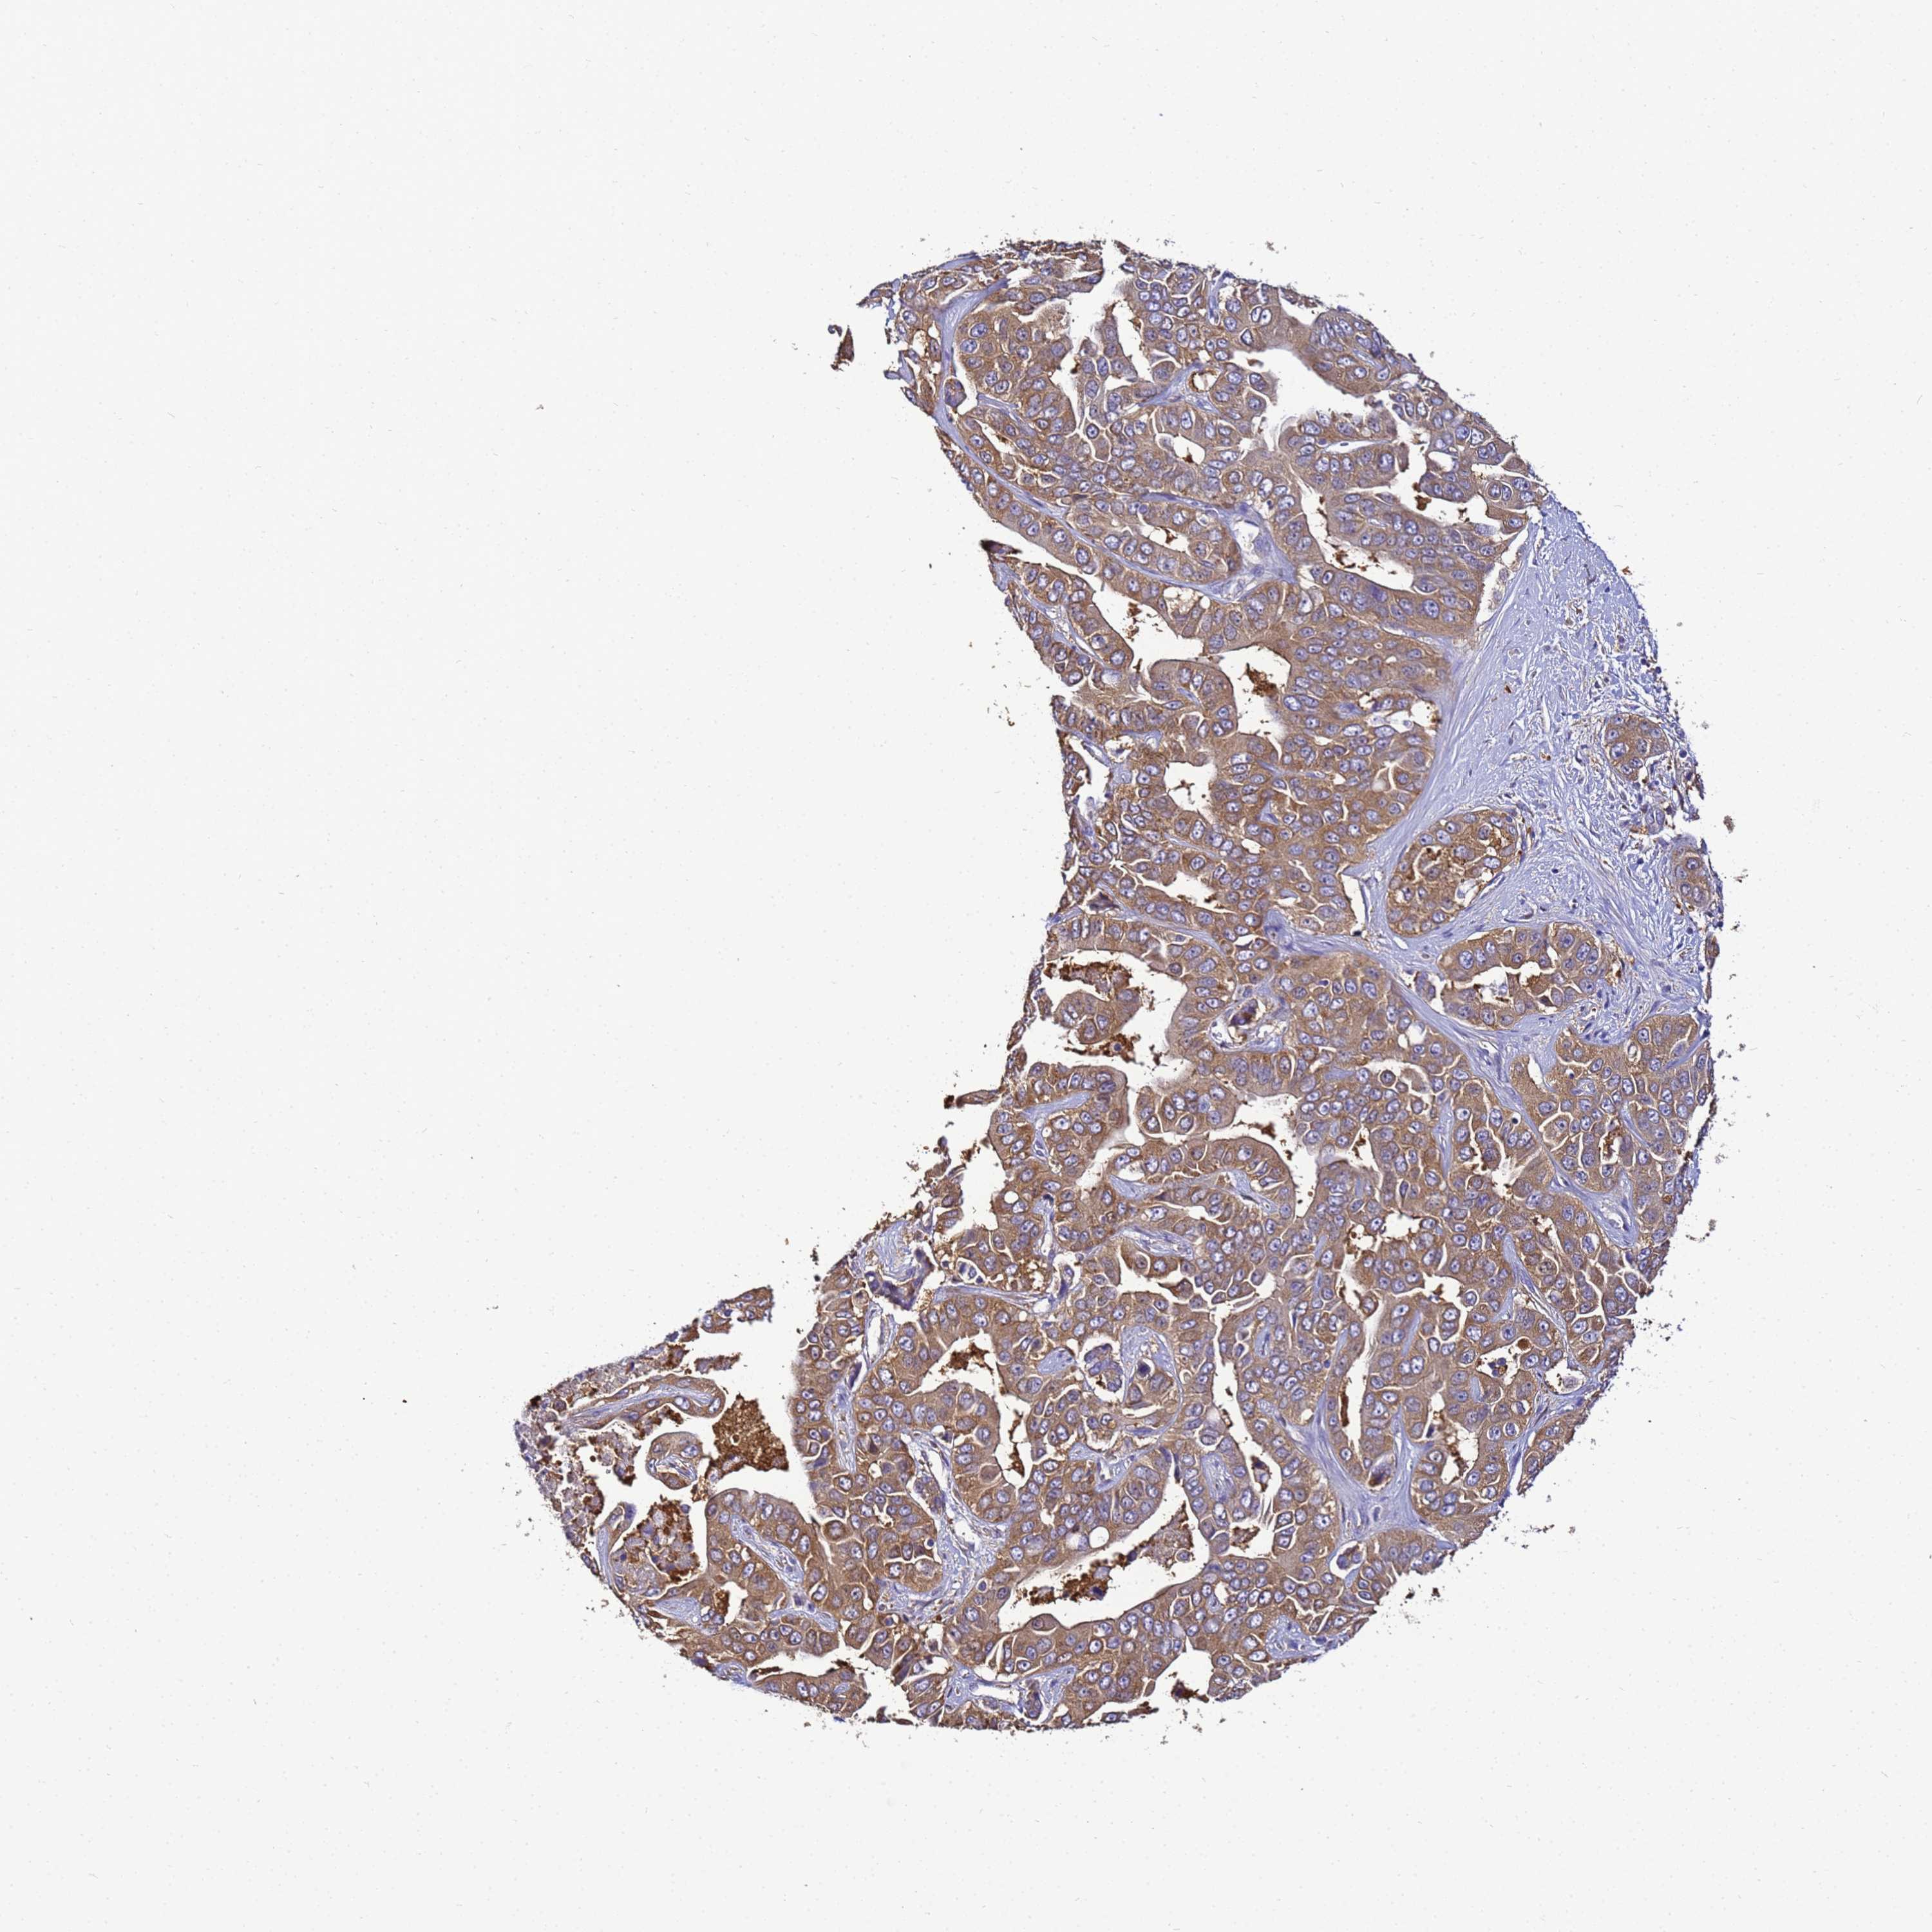

LIVER CANCER - Protein expressioni

A mouse-over function shows sample information and annotation data. Click on an image to view it in a full screen mode. Samples can be filtered based on level of antibody staining by selecting one or several of the following categories: high, medium, low and not detected. The assay and annotation is described here.

Note that samples used for immunohistochemistry by the Human Protein Atlas do not correspond to samples in the TCGA dataset.

Antibody stainingi

Antibody staining in the annotated cell types in the current human tissue is reported as not detected, low, medium, or high, based on conventional immunohistochemistry profiling in selected tissues. This score is based on the combination of the staining intensity and fraction of stained cells.

Each image is clickable and will lead to virtual microscopy that enables deeper exploration of all samples and also displays staining intensity scores, fraction scores and subcellular localization as well as patient and tissue information for each sample.

Antibody HPA040017

Antibody CAB034257

Staining

High

Medium

Low

Not detected

Intensity

Strong

Moderate

Weak

Negative

Quantity

>75%

75%-25%

<25%

None

Location

Nuclear

Cytoplasmic/membranous

Cytoplasmic/membranous,nuclear

Cholangiocarcinoma

Carcinoma, Hepatocellular, NOS